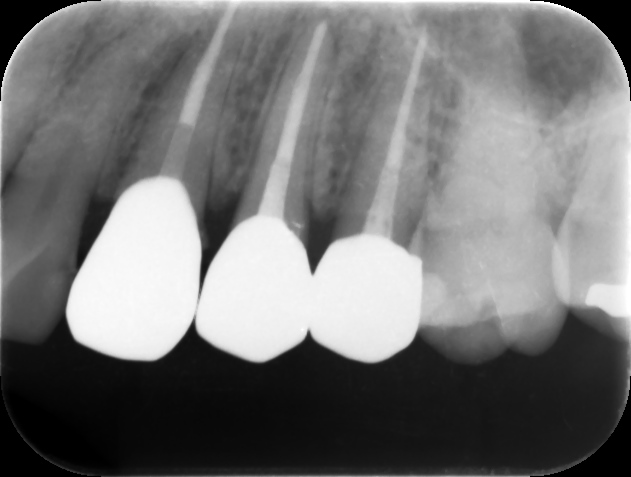

根管充填後レントゲン。歯の痛みや歯茎の腫れが改善したため、バイオセラミックシーラーおよびガッタパーチャにて根管充填を行った。根管治療は2回、2週間で終了。